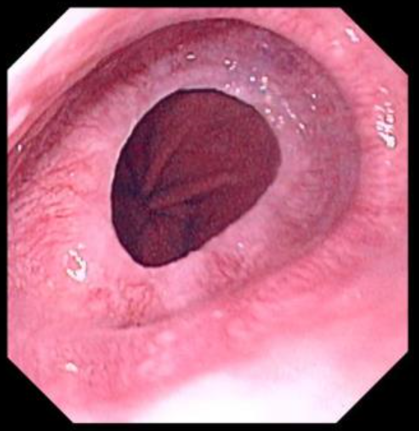

Schatzki’s Ring

Almost all associated with sliding hiatal hernia

Found at squamocolumnar junction

Sx: dysphagia

Dx: barium swallow

Tx: dilation, PPI (not resection)